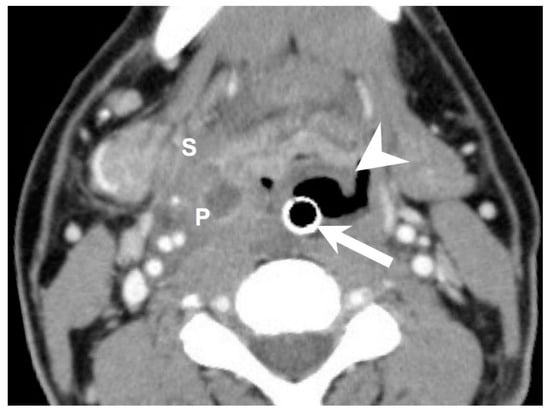

To investigate the risk factors associated with concurrent DNI and AE, we collected data on the patients’ gender, age, hospital stay, C-reactive protein (CRP) level, blood sugar level, diabetes mellitus (DM) status, performance of incision and drainage surgery, number of spaces affected by DNI, deep neck space involvement (Figure 2), presence of mediastinitis, tracheostomy, and species of pathogens involved.

Figure 2. Axial CT view of an intubated patient with concurrent acute epiglottitis and multiple deep neck infections. Abscesses were detected in the parapharyngeal space and submandibular space. Arrow: endotracheal tube insertion; arrowhead: swollen and inflammatory epiglottis; P: parapharyngeal space; S: submandibular space. 300 × 300 DPI.